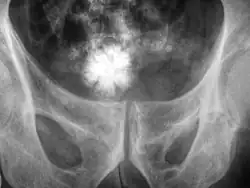

Röntgenbild eines Blasensteins

Für die Diagnostik und Kontrolle ist die Ultraschalluntersuchung die erste Wahl, sowohl in Notfall- als auch in Routinesituationen. Konventionelles Röntgen kann bei schattengebenden Konkrementen angewendet werden, z. B. bei Steinen aus Calciumsalzen.[10]